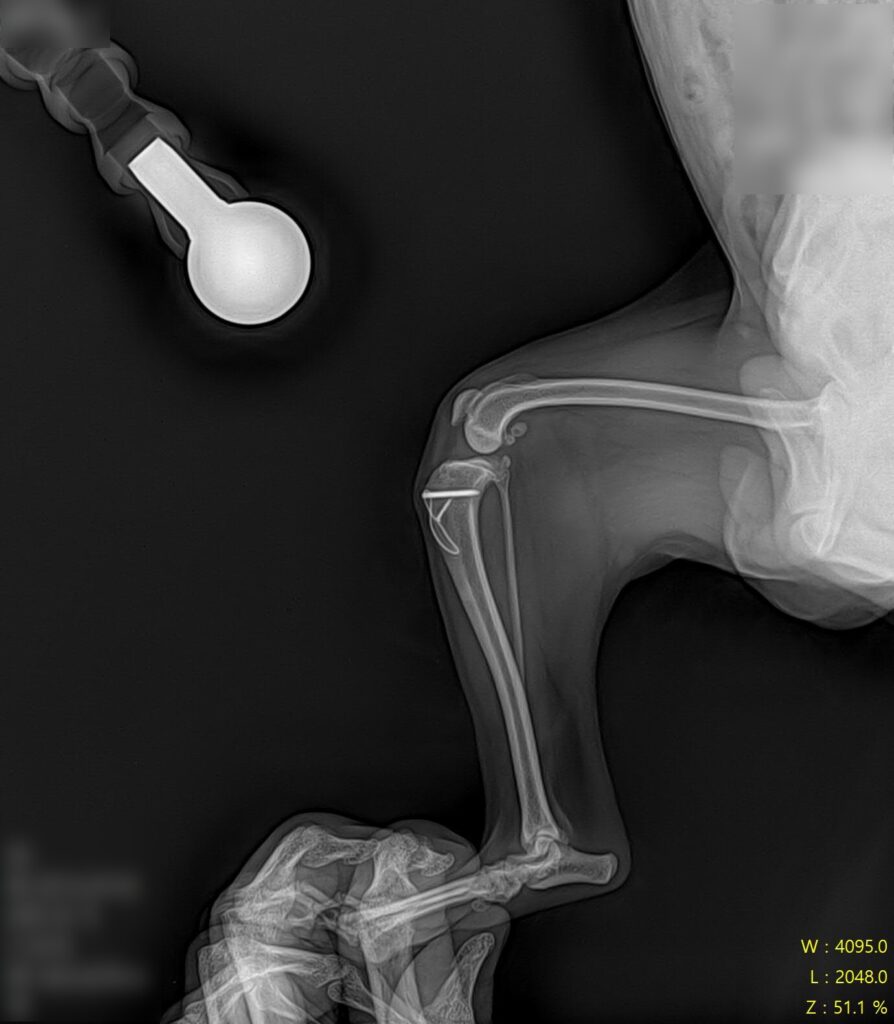

십자인대 수술 후 방사선 검사 사진 / 출처: 라온동물메디컬센터

수술 후에는 통증 관리, 체중 부하 단계 조절, 관절 가동 범위 관리, 근육 회복을 위한 재활 관리를 함께 진행하며 회복 과정을 면밀히 모니터링했습니다. 단계적인 재활 프로그램을 통해 근육을 회복시켜 나간 결과, 봄이는 정상 보행을 회복하여 퇴원하였습니다.